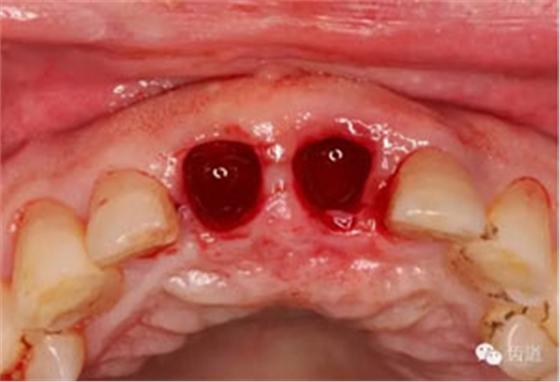

微創(chuàng)拔除根折牙

拔牙窩

探查唇側(cè)骨板(約齦下3-4mm)